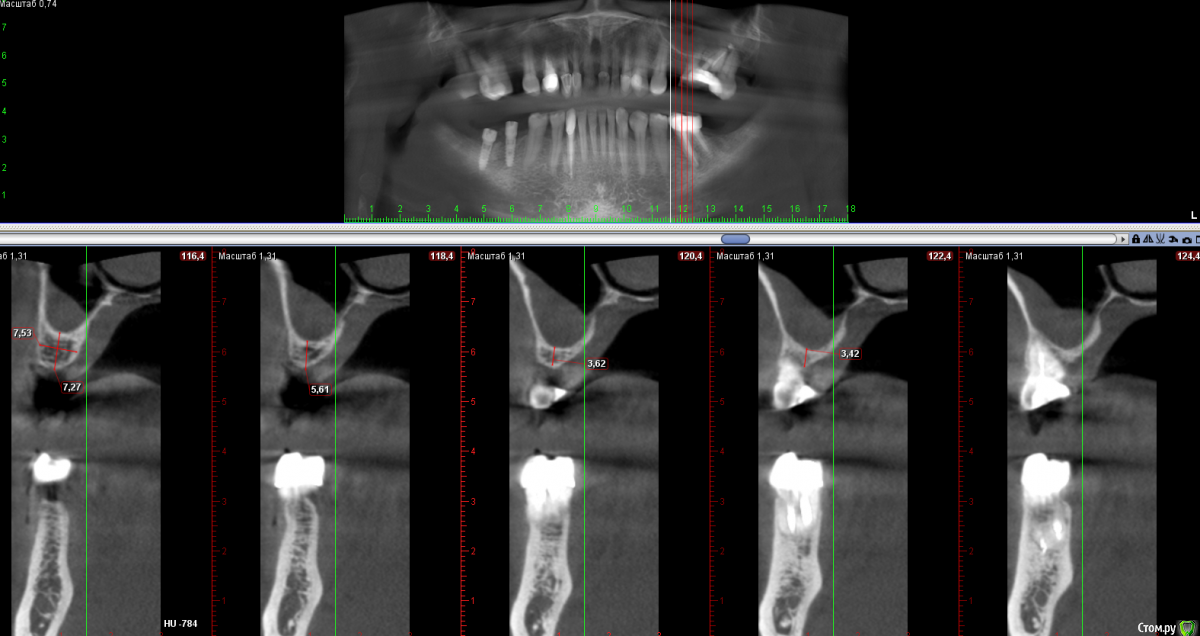

Sampson Опубликовано 23 февраля, 2018 Поделиться Опубликовано 23 февраля, 2018 Первый синуслифтинг. Руки трясутся, пациентка довольная. Ссылка на комментарий

Irouil Опубликовано 23 февраля, 2018 Поделиться Опубликовано 23 февраля, 2018 Выглядит отлично, только как-то скученно Ссылка на комментарий

Sampson Опубликовано 23 февраля, 2018 Поделиться Опубликовано 23 февраля, 2018 Выглядит отлично, только как-то скученноСпасибо,через 6 мес буду ставить 1 имплант в область 2.6.Да, вижу, что получился зиккурат, я еще плохо себе представляю как рассчитать соотношение высоты к основанию объёма,для наметки высоты я засверливаюсь на 3мм ниже будущей "вершины" или "будущего дна пазухи", не понимаю где будут границы основания. Ссылка на комментарий